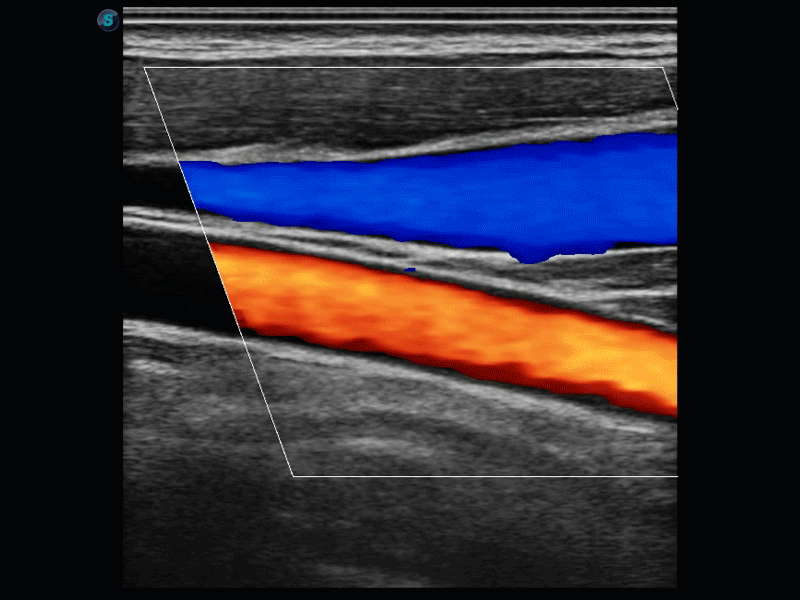

開(kāi)立醫(yī)療通過(guò)不斷的技術(shù)創(chuàng)新,為大眾的生命健康提供持續(xù)關(guān)愛(ài)。P12 Plus采用全新一代超聲成像平臺(tái),新平臺(tái)旨在將真實(shí)還原組織解剖結(jié)構(gòu)作為首要目標(biāo)。平臺(tái)采用全新集成化硬件模塊,搭載新一代芯片,系統(tǒng)性能得到大幅提升,為您的診斷提供了豐富的臨床信息。優(yōu)異的圖像表現(xiàn),豐富的探頭配置,全面的應(yīng)用功能,為您日常診斷提供了可靠的助手。

彩色多普勒超聲診斷系統(tǒng)